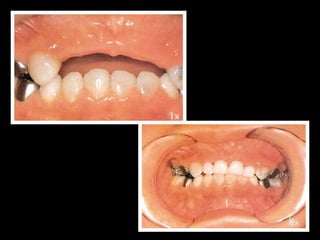

Restauração

de

dentes

anteriores

• Coroas

• Pinos

intra‐radiculares

Pinos

• #16 No caso de pino intrarediculares, deve avalia condição da risolise\n

• #17 Coras de aço com faceta de acrilico .\nMoldagem, dente não sofreda desgaste\n